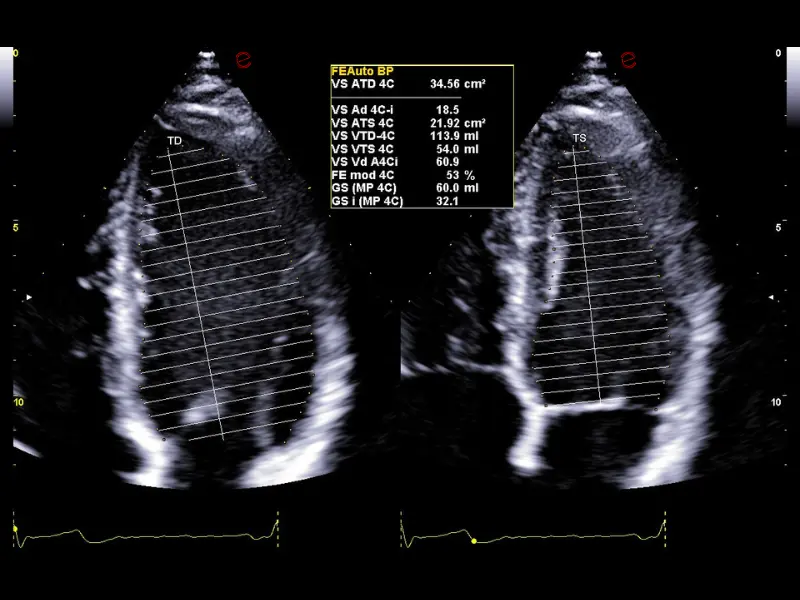

The MyLab™C30 compact ultrasound machine is specifically designed to meet the demands of everyday clinical practice for fast ultrasound access, versatility of use, and space constraints. All this has been achieved without compromising image quality and ultrasound performance. By sharing advanced imaging technologies and transducers with our high-end systems, the MyLab™C30 delivers high quality images and clinical information in a truly compact ultrasound device.

Elevated performance for enhanced diagnostic insights

Featuring the ClearWave Architecture, which combines Esaote’s advanced XBeamforming and XSmart Postprocessing technologies, the MyLab™C30 incorporates state-of-the-art imaging technologies to set a new standard for image quality, giving professionals diagnostic confidence wherever they need it. Maximize the performance of the MyLab™C30 with its wide range of probes for all clinical needs, from daily routine to the most advanced expectations. Equipped with a wide range of advanced features and an accelerated workflow powered by Artificial Intelligence, the MyLab™C30 is your portable ultrasound device that knows no boundaries.